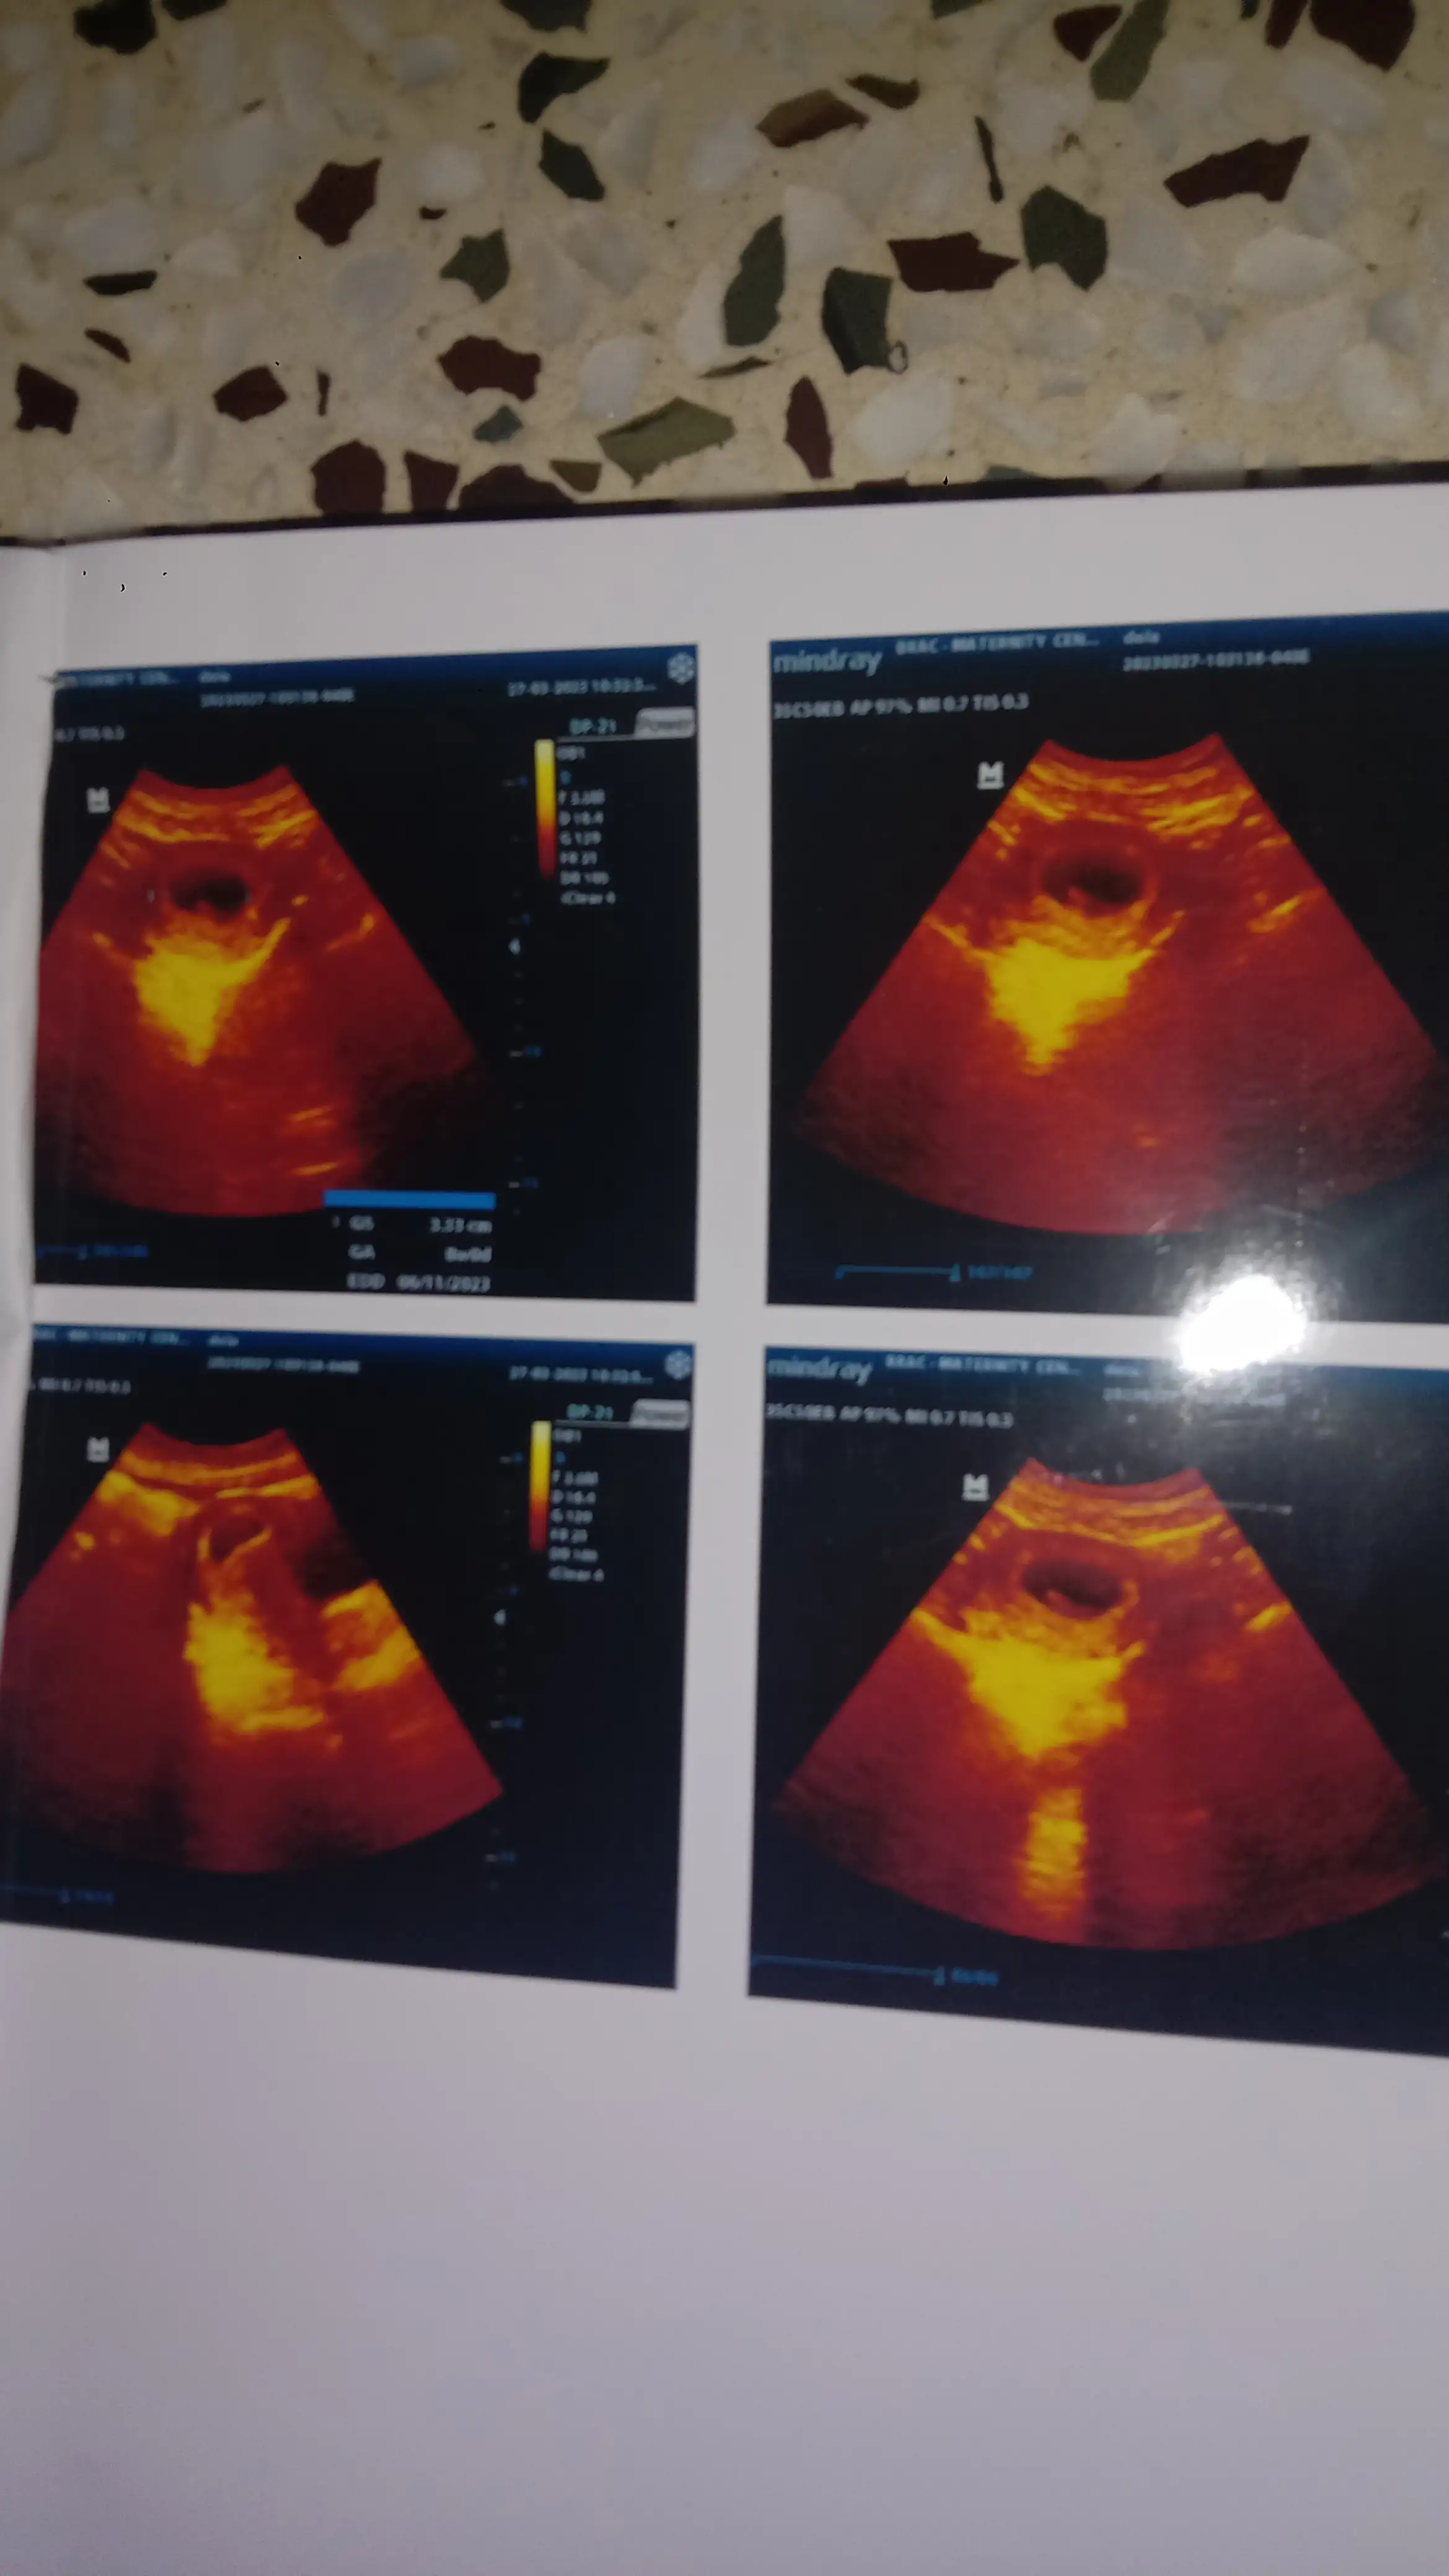

Pregnancy